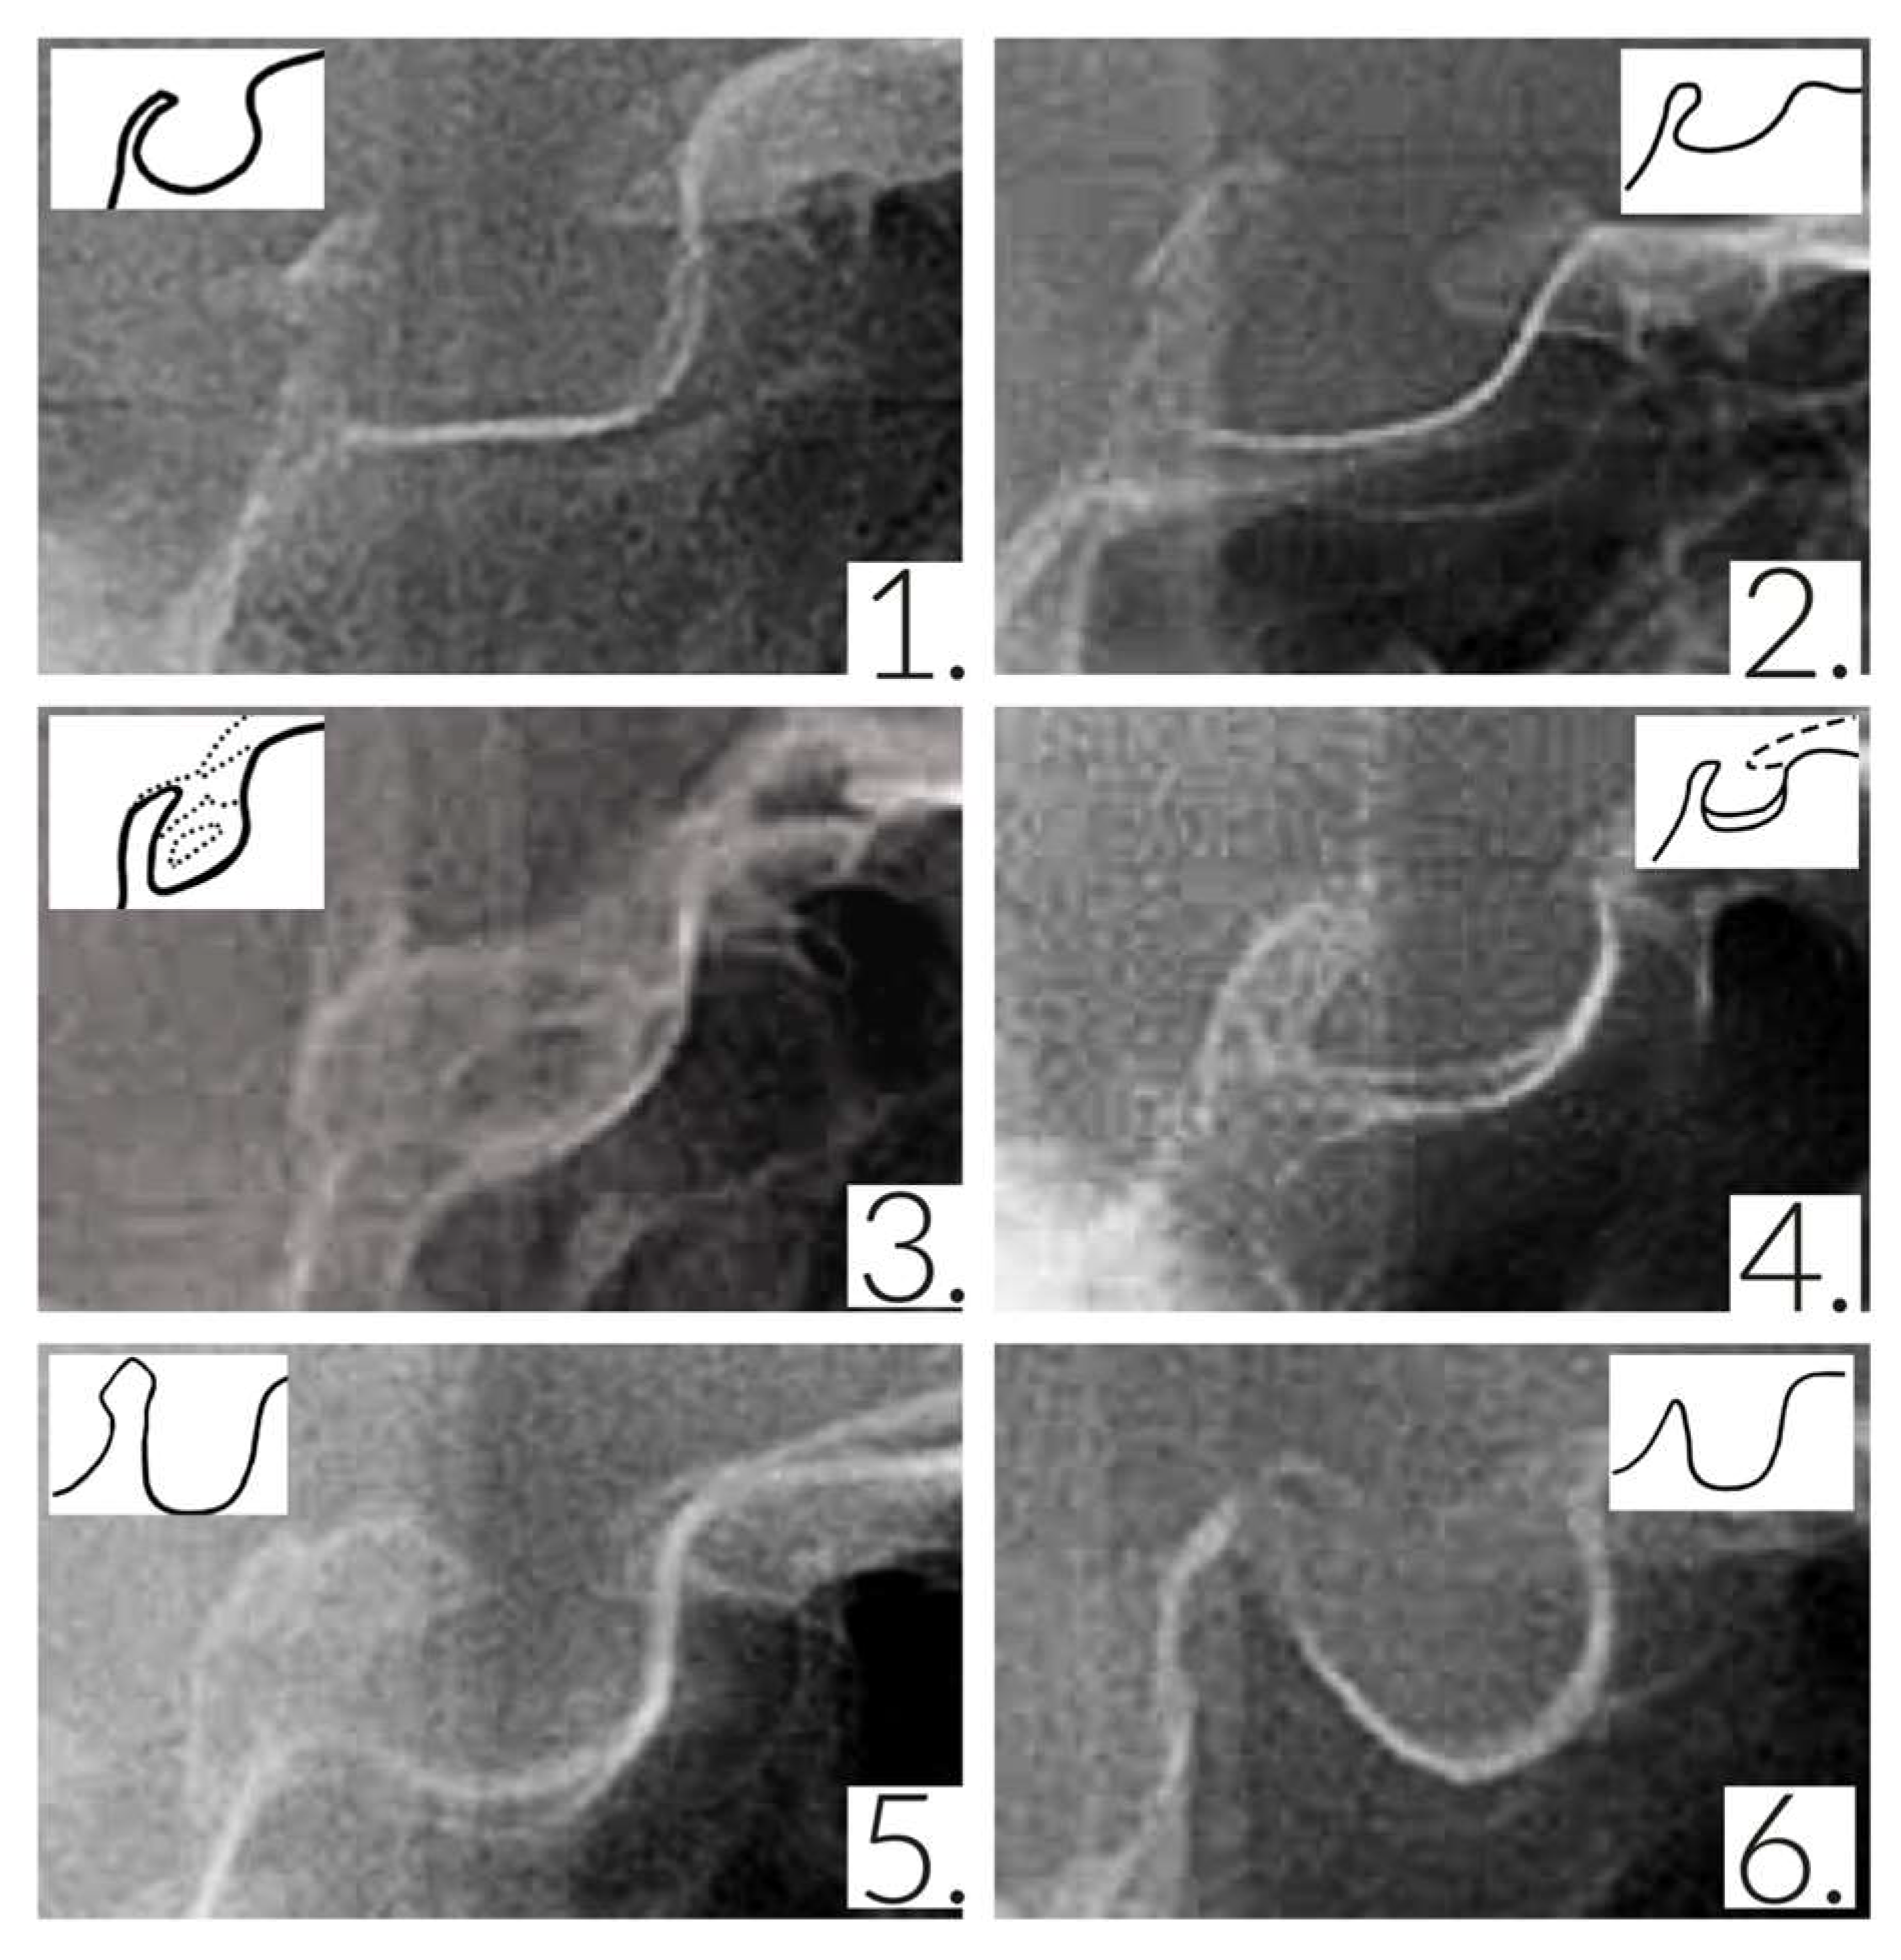

2.4. Assessment of ST Morphology